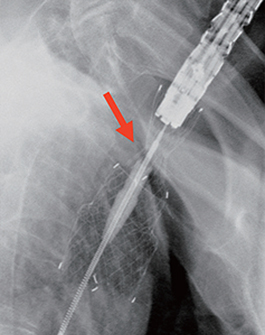

(A) The lesion was located 16cm from the incisors, 1cm below the upper esophageal sphincter (B) Post-stenting radio-graph, showing well positioned cervical stent